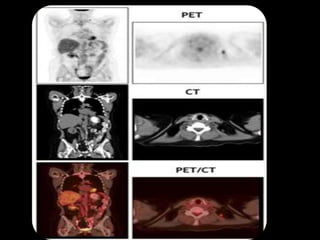

Hybrid Imaging

• PET-CT: radionuclide imaging devices

• The resulting images display the

functional data obtained from the

radionuclide distribution (usually in

color) overlaid on the anatomical

information from CT (usually in grey

scale)